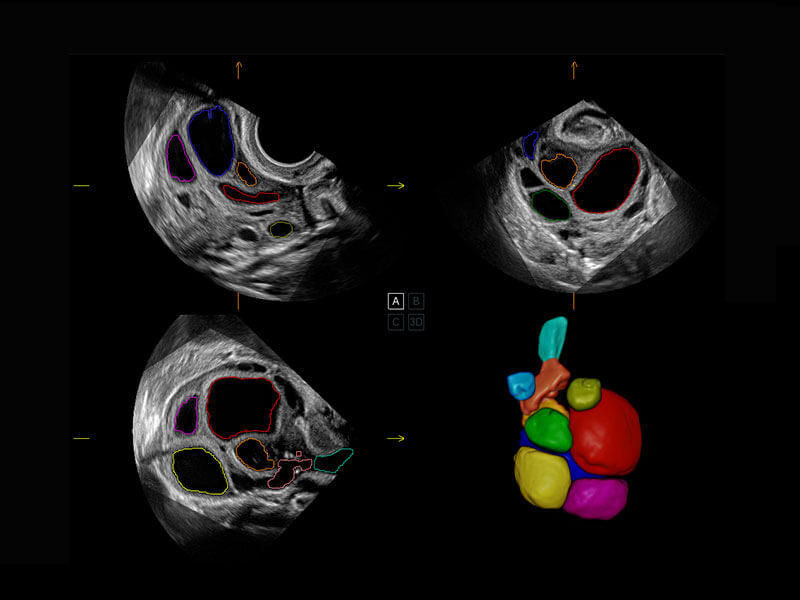

胎心容积成像